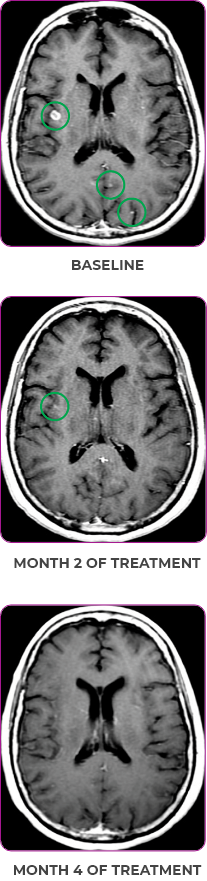

PATIENT CASE:

METASTATIC, RAIa-REFRACTORY,

PAPILLARY THYROID CANCER1

- 56-year-old female with PTCa that had metastasized to multiple sites, including the brain

- Progression after first- and second-line systemic treatment

- PRa after 4 weeks on VITRAKVI® (larotrectinib); CRa after 8 weeks

- At last assessment, complete response was sustained over an 11-month period

Response to VITRAKVI1

- After 8 weeks on VITRAKVI, all target lesions had disappeared, demonstrating a complete response

- The complete response was sustained over 11 months of treatment with VITRAKVI

- Patient experienced Grade 1 fatigue and mild hepatic enzyme elevation

Response in primary and metastatic lesions1

MRIa imagery of the lungs. Arrow indicates large target lesion in left lung.1

SCAN 1: LUNG

MRIa imagery of the brain. Arrow indicates large target lesion in left lung.1

aMRI, magnetic resonance imaging.

Images courtesy of Dr Fabian Pitoia.